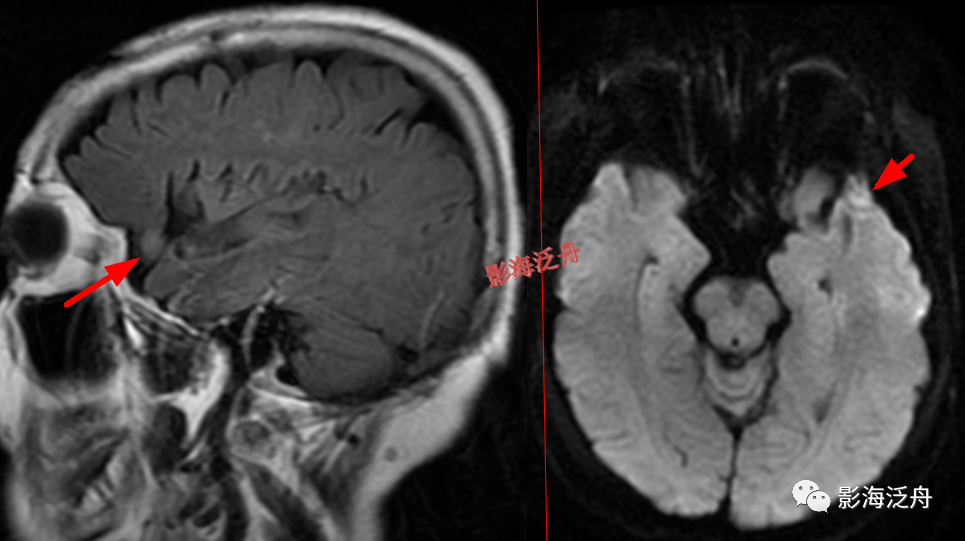

左侧颞部脑膜瘤,在T1WI、T2WI、Flair、DWI四个序列上都非常接近脑实质的信号。这么小的脑膜瘤在MR平扫上漏诊率极高,避免漏诊的办法就是把颅脑解剖学好,然后看片子的时候把脑沟快速地捋一遍,脑沟发生形态改变的区域重点观察。

延髓左侧小梗死灶。这种斑点状的梗死灶漏诊也非常多见,患者症状一般不明显,我自己漏诊过两次。小的梗死灶多见于脑干、侧脑室周围,大脑皮层区一般不多见。因此,重点区域进行细致观察,可以减少此类疾病的漏诊。